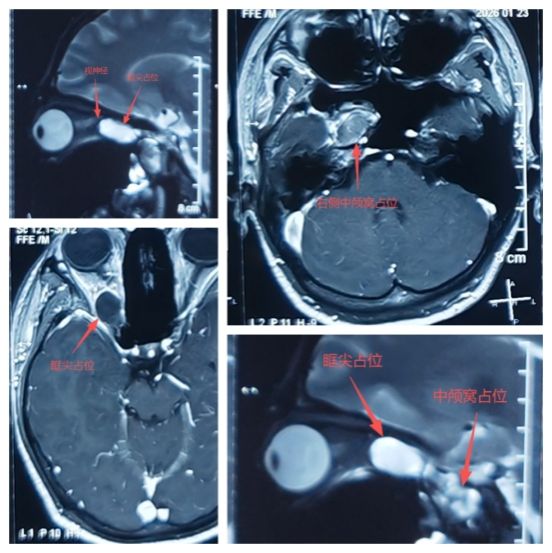

17岁的女孩小张(化名)近两个月来视力莫名下降、视物模糊,起初她以为是看书疲劳引发的近视,并未放在心上。直到3天前,小张突然出现头痛、恶心、食欲不振等症状,家人才察觉异常,带其在外院做头颅CT检查,结果提示右侧Meckel腔囊性占位,且肿瘤已突入眼眶尖部。

焦急的家人经人介绍,带着小张来到我院神经外科二病区,求助郭清保主任团队。经详细检查后确诊,小张颅内的占位性病变已通过视神经管长至眼眶尖部,直接压迫视神经,这正是导致她视力变差、视野缺损的根本原因。

“眶尖区域结构复杂,神经和血管密布,肿瘤还贯穿颅内外,若不及时手术切除,患者极有可能出现永久性视力下降,甚至失明,而手术稍有不慎,也会对周边神经血管造成不可逆的损伤。”郭清保主任表示,保住患者的视力,是此次手术的核心目标和第一要义。

为确保手术成功,郭清保主任团队制定了精细的手术方案,在显微镜下开展微创操作。手术的关键环节,是小心磨除眶尖后壁骨质——既要通过这一步充分暴露深部病灶,为肿瘤切除创造条件,又要全程精准保护视神经,避免分毫损伤。凭借娴熟的显微外科技术和丰富的颅底外科诊疗经验,郭清保主任带领团队逐层突破手术难点,成功将贯穿颅内外的肿瘤完整切除,且眶尖周边结构保护完好,视神经实现全程“零损伤”。